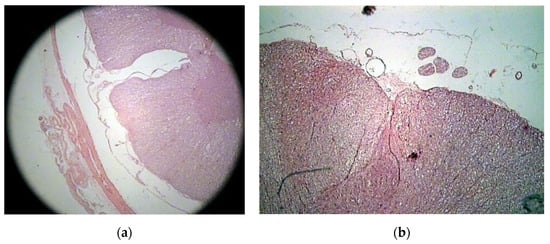

The histologic study on bony specimens at the osteotomized surface showed the presence of live osteocytes and osteoblasts in 92% of cases (Figure 2). Harvested spinal cord in 17 postmortem cases allowed to appreciate the anatomical integrity of both the dura and the neural tissue (Figure 3).

Figure 2.

Histologic study executed on a dog’s bone specimen. Hematoxylin–eosin 2.5X (a) and 10X (b), showing the presence of live osteocytes and osteoblasts near the osteotomized surface (arrowheads).

Figure 3.

Histologic study executed on a cat’s spinal cord. Hematoxylin–eosin 2.5X, showing the perfect anatomical integrity of the spinal cord and dura after piezoelectric osteotomy (a,b).